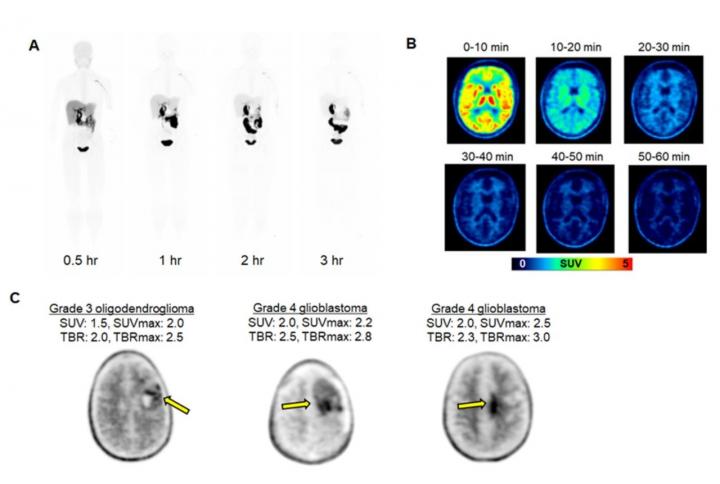

image: Clinical evaluation of [18F]DASA-23. A. Whole body PET maximum-intensity-projection images at different time points after [18F]DASA-23 administration in a healthy volunteer. B. Representative axial [18F]DASA-23 PET images of a healthy human brain at various summed time points post tracer administration. C. Representative 30-60 minute summed [18F]DASA-23 PET images in patients with intracranial malignancies. Standardized uptake values (SUV) and tumor-to-brain (TBR) values are shown.

Image created by C Beinat et. al, Stanford University, Stanford, CA.

The study focused on patients with glioblastoma brain tumors, as normal brain cells have very low levels of PKM2. Healthy volunteers and patients with glioblastoma underwent positron emission tomography/magnetic resonance imaging with 18F-DASA-23. The radiopharmaceutical was successful in visualizing PKM2 in glioblastoma patients, while it was rapidly cleared from the bodies of healthy volunteers.